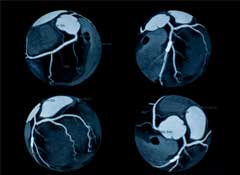

Why? I'm concerned that people who undergo the test, which uses multiple CT scans to produce a three-dimensional image of the heart, often go away thinking either that they are free of the disease or, if the results are worrisome, that it saved their life by identifying heart disease early. But the study published today found that while people who got the test were more likely to be treated aggressively, including with invasive and potentially risky procedures, they were not less likely to have a heart attack or other coronary event. In addition, the study hinted that people with reassuring test results might be less likely to continue healthy lifestyle changes.

The study looked at 2,000 healthy South Korean adults. Half had CT angiography and half had standard care, including routine checks of their blood pressure and cholesterol levels. After 18 months, the 215 people who had worrisome CT scans were more likely to have additional tests and be prescribed aspirin and cholesterol-lowering drugs than people who didn't have the test. And some even had angioplasty or heart bypass surgery. But they were no less likely to have a coronary event.

That's a point we've been making for years, particularly for CT angiography. Why? For one thing, the test exposes patients to potentially cancer-causing radiation, sometimes significant amounts. Moreover, while the test can identify blockages in the coronary arteries, researchers increasingly understand that heart disease is much more than just a "plumbing problem" caused by those blockages. Instead, it's a systemic disease of the arteries that also involves inflammation, clotting abnormalities, and numerous other factors. Simply identifying and treating the blockages fails to address the underlying problems or the real causes of heart attacks and heart disease. In fact, we've said since 2007 that medication and lifestyle change can be as effective as angioplasty in treating many patients with coronary obstructions. Finally, many if not most of us, lead long healthy lives with some obstructions in our heart arteries that never cause a problem.